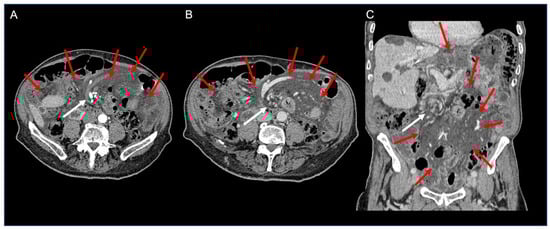

| Case 1—2020 | M | 41 | left flank pain with nausea and costipation | mini gastric bypass | contrast CT | exploratory laparotomy | yes | no | no | yes (2) | 6th POD | 1724 | negative | negative for malignacy | ||

| Case 2—2022 | M | 83 | abdominal pain and costipation | lower limb melanoma excision | PLT 126,000, LDH 248, CPK 387 | contrast CT | exploratory laparotomy | yes | yes | no | yes (2) | 7th POD | 2488 | negative |